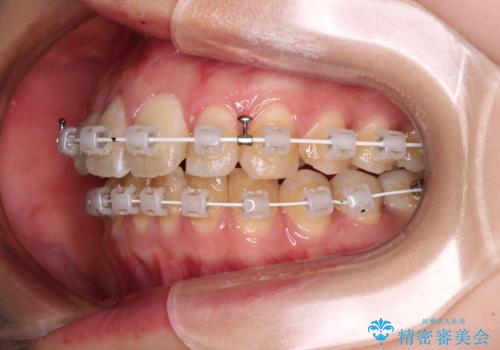

- 矯正装置

- 審美装置

- 1年5ヶ月

- 10-30回

奥歯の咬み合わせ改善が必要であるため、マウスピース矯正より確実に達成のできるワイヤー矯正にて治療を行うこととしました。

奥歯の咬み合わせはしっかりと改善され、前歯の突出感も改善されました。